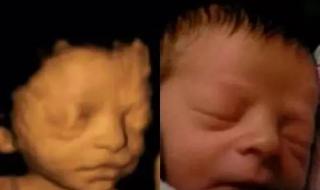

胎儿四维彩超照片

四维彩超是最先进的超声诊断设备,能够对胎儿进行超声检查,可以立体的显示胎儿的颜色,还有面部各个器官等发育的情况,同时对胎儿的畸形,比如唇裂、腭裂、骨骼发育异常都能够尽早的做出判断,一般在怀孕24周到28周的时候,是可以进行四维彩超的。